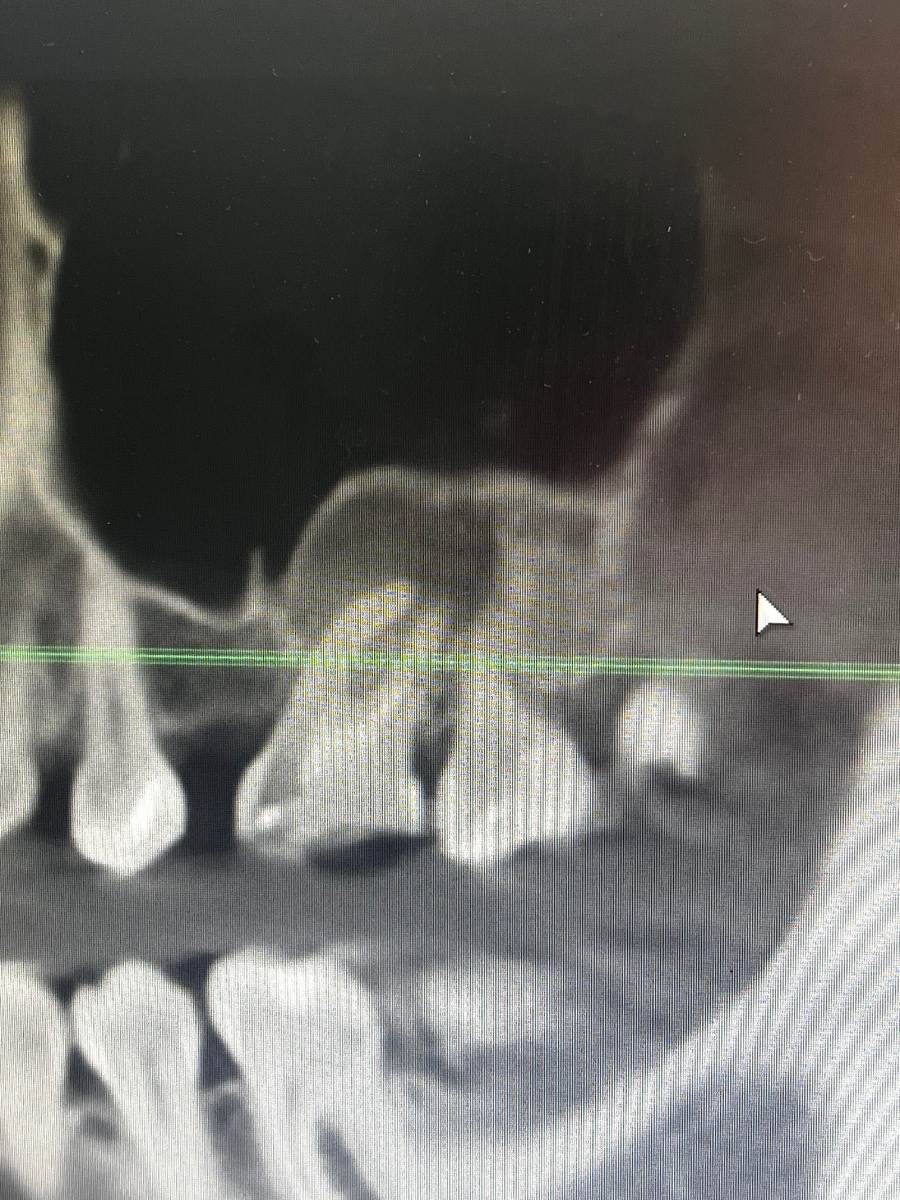

МиланаМ Опубликовано 3 часа назад Поделиться Опубликовано 3 часа назад Добрый день, подскажите, пожалуйста, на снимке это киста или просто хроническое воспаление ? Я так понимаю, что капсула, которая должна быть у кисты здесь отсутствует Ссылка на комментарий

Женька Опубликовано 2 часа назад Поделиться Опубликовано 2 часа назад @МиланаМ Здравствуйте, киста - диагноз который ставится на основе микроскопического исследования. Поэтому по снимкам, на 100% это утверждать не возможно. С высокой долей вероятности это периодонтит (воспаление окружающих зуб тканей). В любом случае зуб требует лечения. Ссылка на комментарий

МиланаМ Опубликовано 2 часа назад Автор Поделиться Опубликовано 2 часа назад @Женька А какова вероятность успешно это пролечить консервативно? Или удаление имеет место быть? Ссылка на комментарий

Женька Опубликовано 1 час назад Поделиться Опубликовано 1 час назад @МиланаМ Одного только этого среза недостаточно, чтобы говорить об успехе. Однако, вероятность успеха будет очень сильно зависеть от квалификации эндодонтиста, который этим зубом будет заниматься. Но переменных очень много, которые решаются непосредственно во время лечения. Удалить всегда успеете, как говорится. Ссылка на комментарий